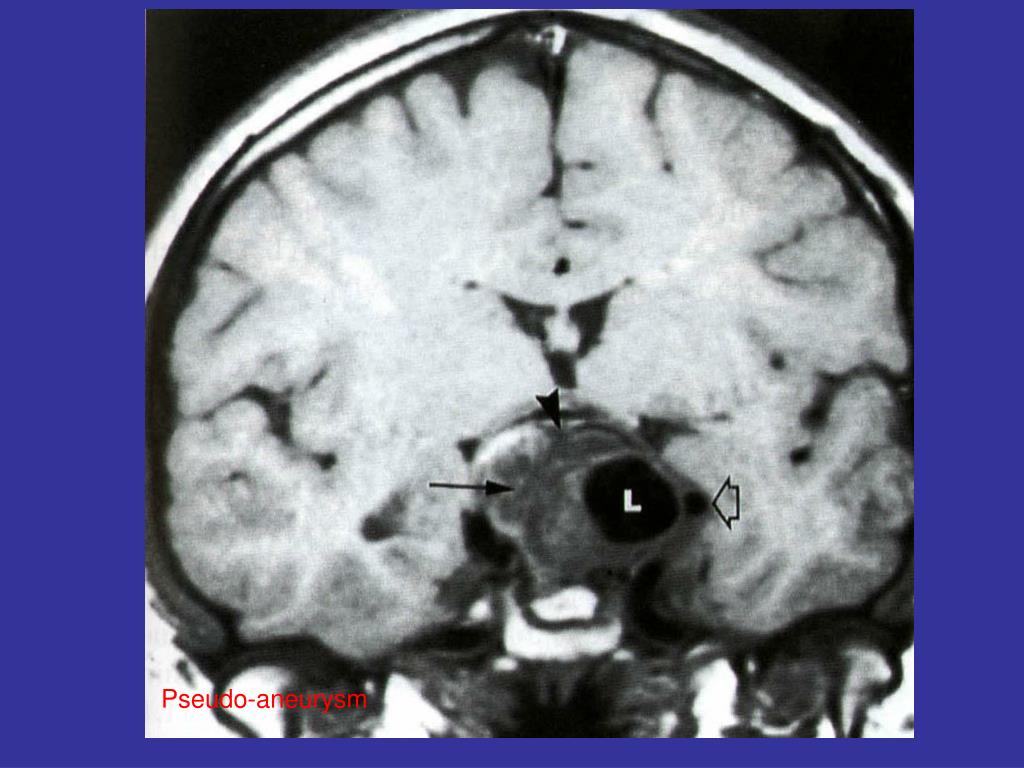

19. Vascular damage • Dissection of internal carotid artery • Carotid-cavernous fistula • Pseudo-aneurysm

22. Pseudo-aneurysm